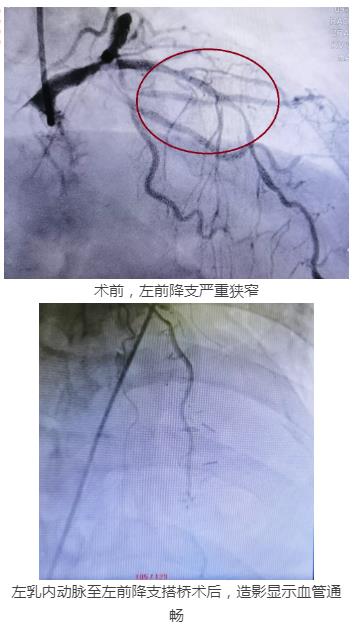

家住长沙的60岁向嗲嗲平时喜爱爬山、跳舞。但近1个月来,他常感到胸痛、胸闷、呼吸困难。几经辗转,向嗲嗲来到捷克论坛 心内三科求诊。经冠状动脉造影检查发现,其三支血管严重狭窄,左前降支呈现弥漫性狭窄90%以上,左回旋支也存在95%以上狭窄。

6月3日,医院心外、心内两组专家依次上阵。先由心胸外科专家团队从患者左侧第5肋间取10cm切口后,在跳动的心脏上进行左乳内动脉—前降支搭桥术。这是为患者解除了心脏三根主血管中最主要的一支——左前降支的险情,恢复血流并为后面的介入治疗提供安全保障。搭桥手术结束后,心血管内科介入专家团队立即对其施行冠脉支架植入术,在回旋支成功植入一枚药物支架。经过5个小时的杂交手术后,患者堵塞的血管成功疏通,血运障碍顺利解除。术后两天,患者就能下床行走。